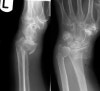

X-ray : 원위 요골 골절(Smith fracture)

2. Smith 골절 : Colles 골절과 반대로 골절 부위의 먼쪽이 아래 또는 앞쪽으로 전위됩니다.